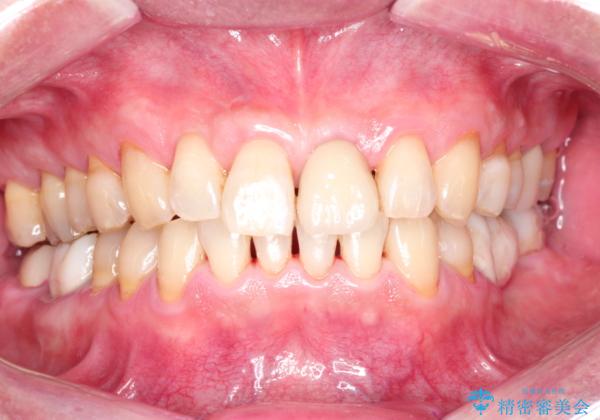

- 日頃の積み重なった茶渋・着色をエアフローにてクリーニングしました。

- 12000円+TAX (PMTC“エアフロー”60分コース)費用は治療当時の料金となります

歯についている茶しぶやタバコによるヤニは着色を落とす専用器具を使用しないと綺麗に取り除くことはできません。

歯の表面に着色が付いて黄ばんで見えることがあるため、PMTCを行うとご自身の歯本来の色味にすることができます。